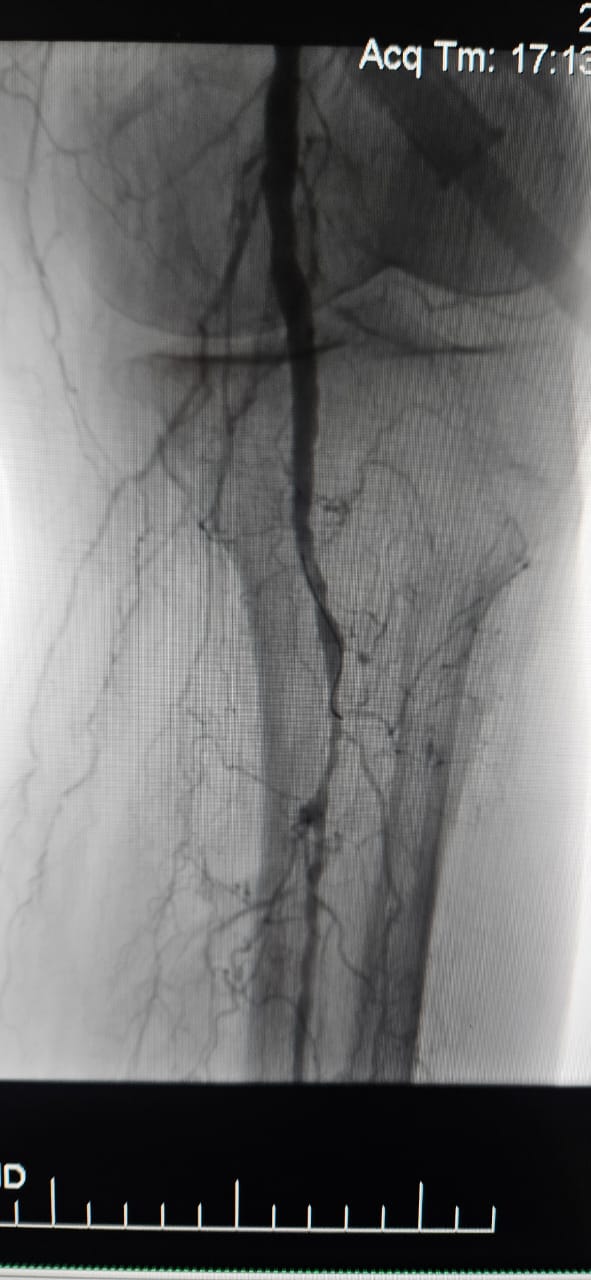

Siamo lieti di condividere un caso di successo da un ospedale di Batumi, in Georgia, dove una paziente di 78 anni con ischemia degli arti critici (CLI) causata dall'occlusione totale cronica dell'arteria degli arti inferiori ha mostrato un notevole miglioramento clinico dopo il trattamento con il Sistema catetere di dilatazione del palloncino IVL periferico ThorCrack.

Questo caso sottolinea il valore clinico della litotripsia intravascolare (IVL) nel trattamento di casi CLI complessi con occlusione cronica a segmento lungo, in particolare nei pazienti con calcificazione pesante, dove i palloncini tradizionali o i dispositivi di aterectomia possono avere un'efficacia limitata.